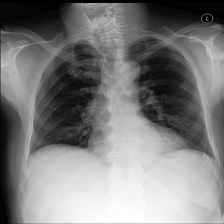

Measure radiology report generation quality Automatic natural language generation (NLG) metrics do not provide sufficient evaluation of the clinical applicability of AI-generated radiology reports. We therefore performed expert radiologist evaluation of AI-generated reports on the MIMIC-CXR dataset, including comparison to the radiologist-provided reference reports.

To further assess the quality and clinical applicability of chest X-ray reports generated by Med-PaLM M and understand the effect of model scaling, we conducted a human evaluation using the MIMIC-CXR dataset. The evaluation was performed by four qualified thoracic radiologists based in India.

Dataset

The evaluation set consisted of 246 cases selected from the MIMIC-CXR test split. To match the expected input format of Med-PaLM M, we selected a single image from each study. We excluded studies that had ground truth reports mentioning multiple X-ray views or past examinations of the same patient.

Procedure

We conducted two complementary human evaluations: (1) side-by-side evaluation where raters compared multiple alternative report findings and ranked them based on their overall quality, and (2) independent evaluation where raters assessed the quality of individual report findings. Prior to performing the final evaluation, we iterated upon the instructions for the raters and calibrated their grades using a pilot set of 25 cases that were distinct from the evaluation set. Side-by-side evaluation was performed for all 246 cases, where each case was rated by a single radiologist randomly selected from a pool of four. For independent evaluation, each of the four radiologists independently annotated findings generated by three Med-PaLM M model variants (12B, 84B, and 562B) for every case in the evaluation set. Radiologists were blind to the source of the report findings for all evaluation tasks, and the reports were presented in a randomized order.

Side-by-side evaluation

The input to each side-by-side evaluation was a single chest X-ray, along with the “indication” section from the MIMIC-CXR study. Four alternative options for the “findings” section of the report were shown to raters as depicted in Figure A.3. The four alternative “findings” sections corresponded to the dataset reference report’s findings, and findings generated by three Med-PaLM M model variants (12B, 84B, 562B). Raters were asked to rank the four alternative findings based on their overall quality using their best clinical judgement.

In a side-by-side evaluation, four clinician raters ranked the quality of four radiology reports, comparing the radiologist-provided reference report from the MIMIC-CXR dataset with reports generated by different Med-PaLM M model scales (12B, 84B, and 562B).

Figure 4(a) summarizes how often each rater ranked a report generated by one of the three Med-PaLM M variants or the reference report as the best among four candidate reports. Averaged over all four raters, the radiologist-provided reference report was ranked best in 37.14% of cases, followed by Med-PaLM M (84B) which was ranked best in 25.78% of cases, and the other two model scales, 12B and 562B, which were ranked best in 19.49% and 17.59% of cases respectively.

To enable a direct comparison of reports generated by each Med-PaLM M model scale to the radiologist-provided reference report, we derived pairwise preferences from the four-way ranking and provided a breakdown for each rater and model scale in Figure 4(b). Averaged over all four raters, Med-PaLM M 84B was preferred over the reference report in 40.50% of cases, followed by the other two model scales, 12B and 562B, which were preferred over the reference report in 34.05% and 32.00% of cases, respectively.

6.3.2 Independent evaluation

We report the rates of omissions and errors radiologists identified in findings paragraphs generated by Med-PaLM M. Figure 5 provides breakdowns by model scales (12B, 84B, 562B). We observed different trends for omissions and errors. For omissions, we observed the lowest rate of 0.12 (95% CI, 0.10 - 0.15) omissions per report on average for both the Med-PaLM M 12B and 84B models, followed by 0.13 (95% CI, 0.11 - 0.16) for the 562B model.

In contrast, we measured the lowest mean error rate of 0.25 (95% CI, 0.22 - 0.28) for Med-PaLM M 84B, followed by 0.28 (95% CI, 0.24 - 0.31) for Med-PaLM M 12B and 0.29 (95% CI, 0.25 - 0.32) for the 562B model. Notably, this error rate is comparable to those reported for human radiologists baselines on the MIMIC-CXR dataset in a prior study [14].

In Figure 6, we illustrate a qualitative example of chest X-ray reports generated by Med-PaLM M across three model sizes along with the target reference report. For this example, our panel of radiologists judged the Med-PaLM M 12B report to have two clinically significant errors and one omission, the Med-PaLM M 84B report to have zero errors and zero omissions, and the Med-PaLM M 562B report to have one clinically insignificant errors and no omissions.